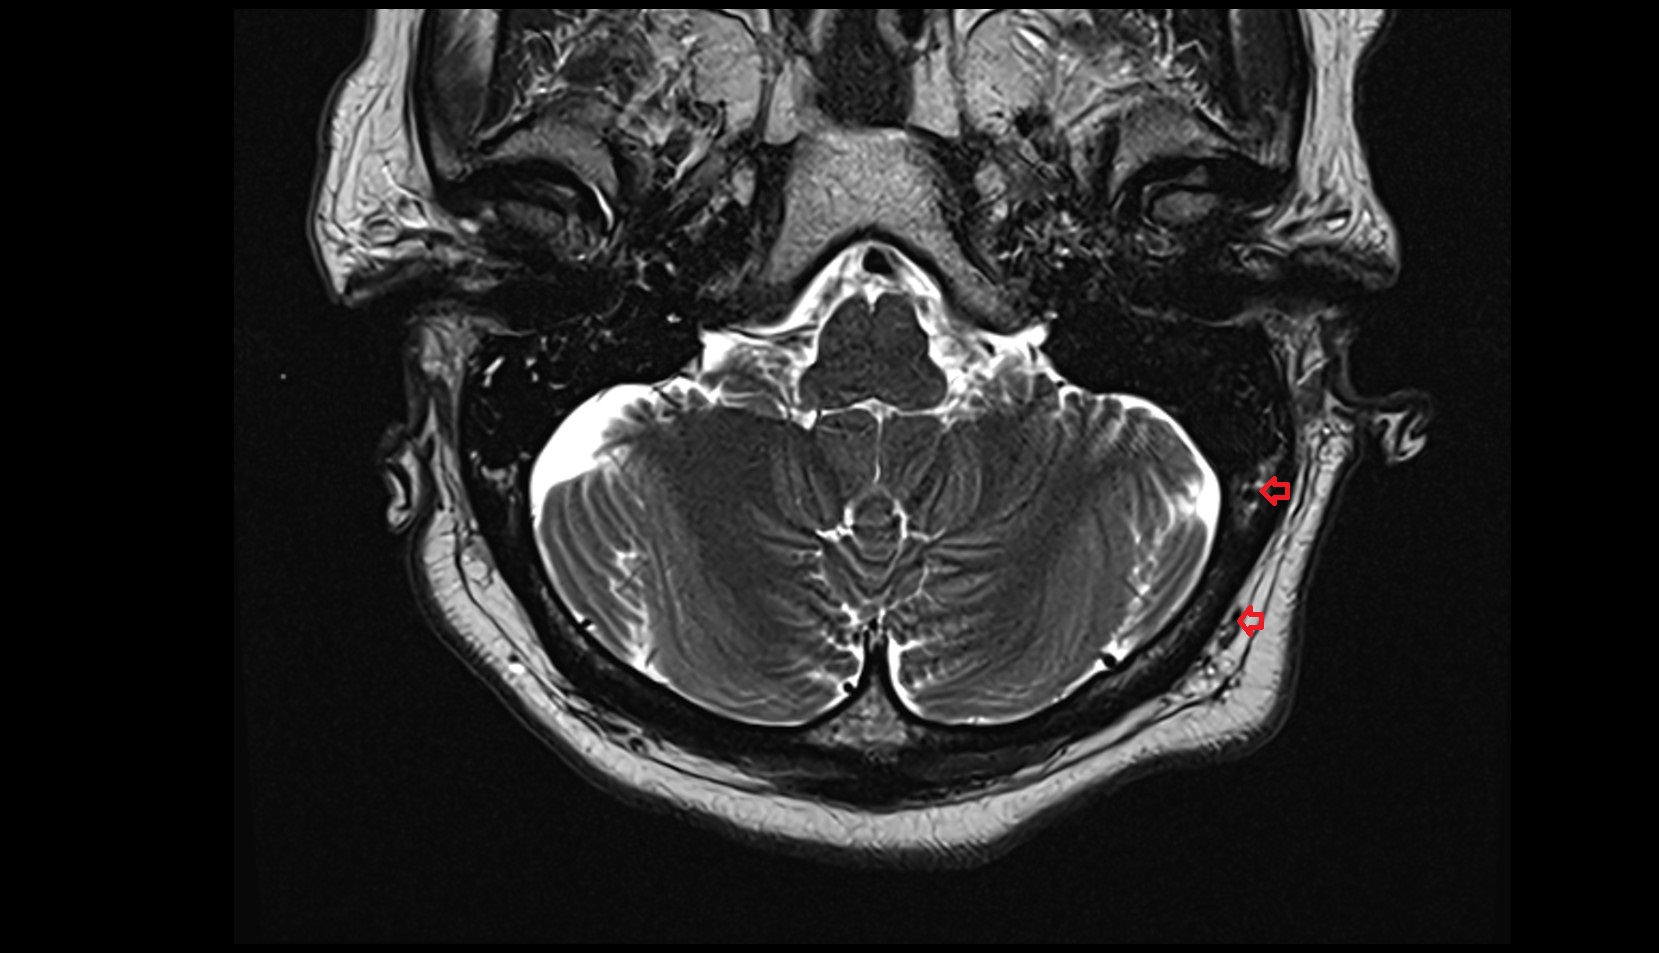

- Cerebellopontine cistern

- Lateral aperture of fourth ventricle (foramen of Luschka)

- Flocculus

- Cerebellar tonsil (H IX)